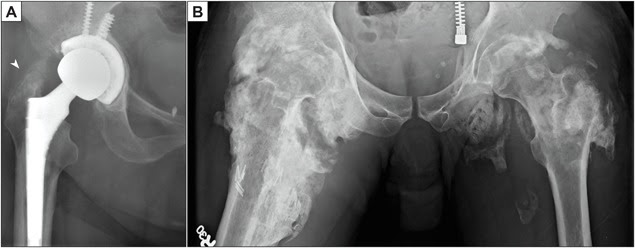

- Sau phẫu thuật chỉnh hình, thường gặp nhất là thay khớp háng,

- X quang đặc hiệu nhưng không nhạy trong cốt hoá lạc chỗ giai đoạn sớm. Có thể mất 3-8 tuần để xương lạc chỗ hiển thị trên phim chụp X-quang. Xương lạc chỗ được mô tả là trông như “mịn như lông” (fluffy) hoặc “giống như bắp rang bơ” (popcorn-like). Giai đoạn ổn định đặc trưng bởi hiện tượng phân vùng mô học với lớp vỏ ngoài xương trưởng thành điển hình.

- Một số phân loại mức độ cốt hoá lạc chỗ trên X quang: Phân loại của Brooker cho khớp háng (phân độ I-IV), Phân loại Hastings và Graham cho khớp khuỷu (phân độ I-II))

- Chụp cắt lớp vi tính (CT): hình ảnh cho hình ảnh rõ hơn X quang thường, và có ích để lập kế hoạch phẫu thuật cắt bỏ.

Chiếu xạ quanh phẫu thuật trong vòng 24 giờ trước phẫu thuật đến 72 giờ sau phẫu thuật có thể phòng ngừa cốt hoá lạc chỗ sau phẫu thuật thay khớp háng toàn phần. Chiếu xạ quanh phẫu thuật ngoài thời gian này có thể làm tăng nguy cơ hình thành cốt hoá lạc chỗ.